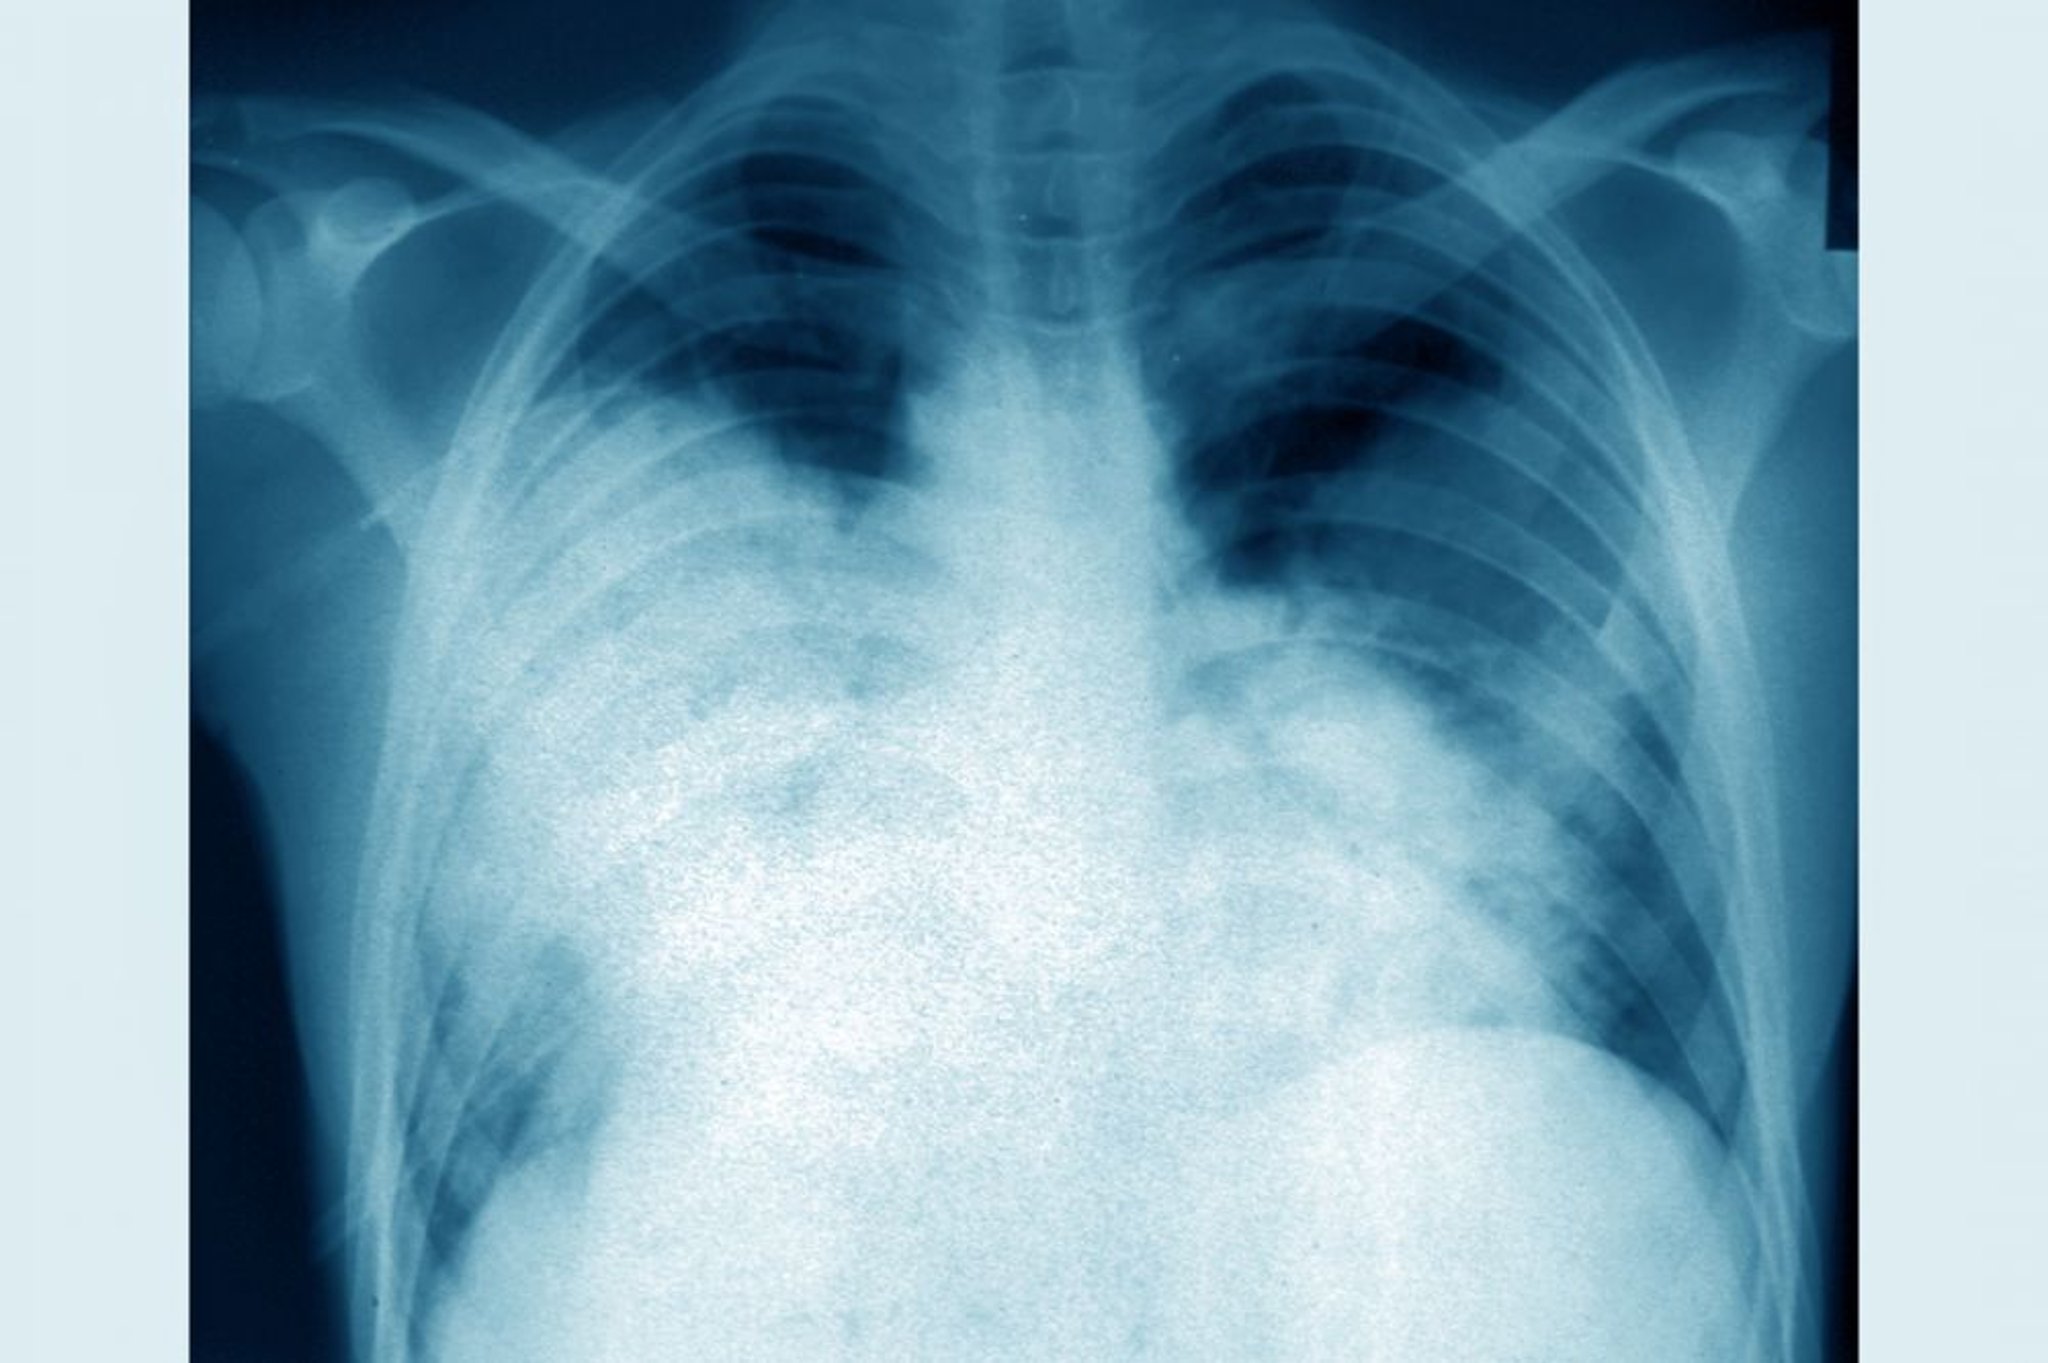

この胸部X線正面像には,急性両側性肺炎(Legionella pneumophilaによるレジオネラ症)が認められる。